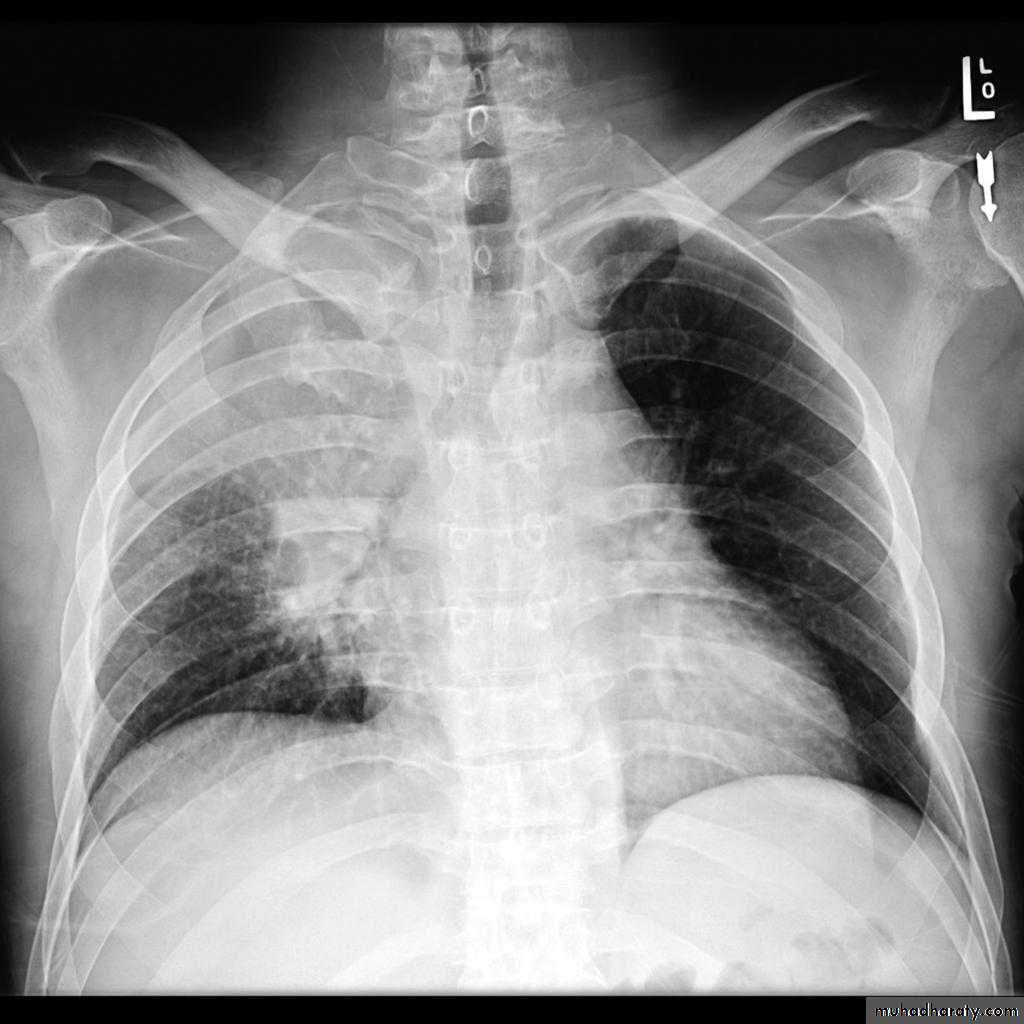

Plain radiograph

Chest x-rays are usually abnormal

1. Tram-track opacities are seen in cylindrical bronchiectasis, and

2. air-fluid levels may be seen in cystic bronchiectasis.

Honey comb shadow

3.Overall there appears to be an increase in bronchovascular markings, and bronchi seen end on may appear as ring shadows .

4.Pulmonary vasculature appears ill-defined, thought to represent peri bronchovascular fibrosis .